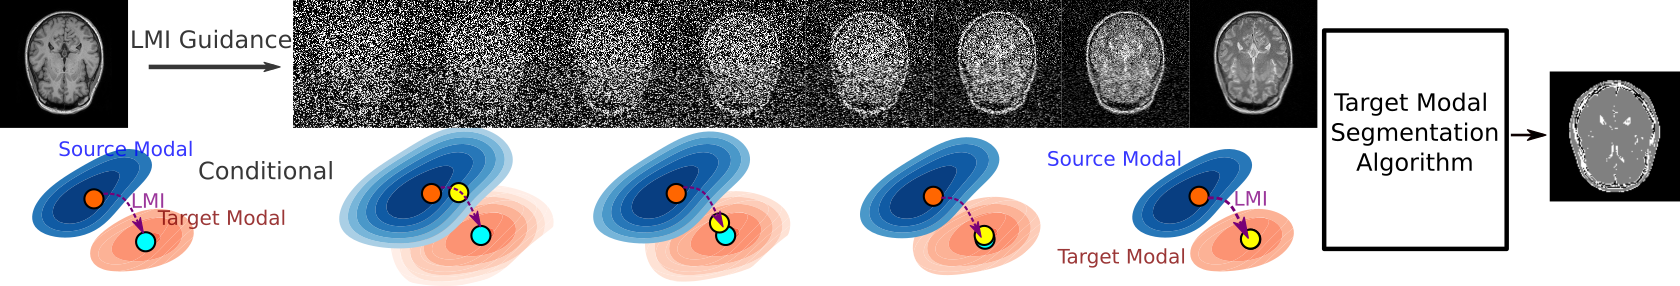

To address the hurdles posed by zero-shot learning in cross-modality translation, our approach leverages statistical feature-wise homogeneity to condition a diffusion model tailored for zero-shot cross-modality image translation. This strategy leverages a connection between the origin and the target modalities, capitalizing on their localized statistical features for accomplishing cross-modality image transition via the diffusion paradigm. Fig. 1 illustrates our statistical feature-driven diffusion model (LMI𝐿𝑀𝐼LMI: Locale-based Mutual Information), which performs zero-shot image translation for cross-modality image segmentation. Our proposition is an unsupervised Zero-shot Learning framework capable of navigating translations amidst previously unseen modalities.

Refer to caption

Figure 1: Schematic diagram shows the LMI-guided diffusion for zero-shot cross-modal segmentation. The blue and orange contours are source and target distributions. The blue dot in the orange contour represents the target datapoint of the source datapoint (orange dot in the blue contour) in the source distribution. LMIDiffusion uses explicit statistical features (LMI) to navigate the next step (yellow dot), providing continuous guidance (yellow dot) from start to finish. In the end, the translated image can be segmented using arbitrary segmentation methods that were trained only on the target modality.